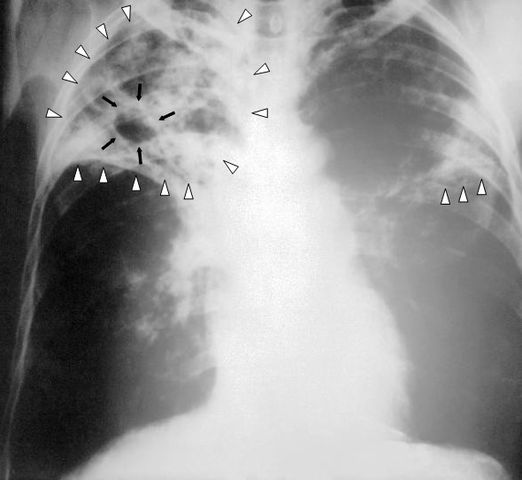

English: An anteroposterior X-ray of a patient diagnosed with advanced bilateral pulmonary tuberculosis. This AP X-ray of the chest reveals the presence of bilateral pulmonary infiltrate (white triangles), and „caving formation“ (black arrows) present in the right apical region.The diagnosis is far-advanced tuberculosis.